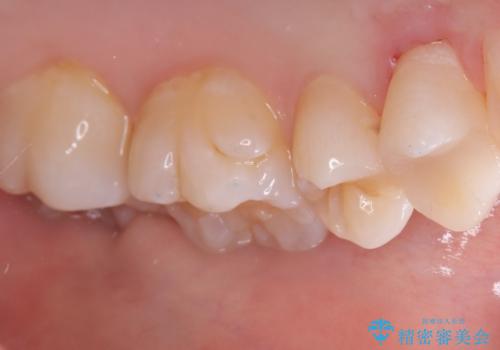

- 主訴:左上真ん中らへんの歯が欠けてしみるので治したい

審美性、適合性の良いセラミックインレーでのやり替えとなりました。

左上4近心に実質欠損を認め、遠心から咬合面にかけてはCR修復が施されていたため、MODインレー窩洞としました。

インレー接着操作時はラバーダム防湿を行っています。